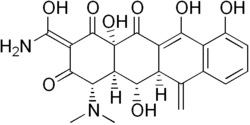

| Nom UICPA | (2Z,4S,4aR,5S,5aR,12aS)-2-[amino(hydroxy)méthylène]- 4-(diméthylamino)-5,10,11,12a-tétrahydroxy-6-méthylène-4a,5a,6,12a-tétrahydrotétracène-1,3,12(2H,4H,5H)-trione |

| Formule | C22H22N2O8 [Isomères] |

| Masse molaire[1] | 442,418 7 ± 0,021 9 g/mol C 59,73 %, H 5,01 %, N 6,33 %, O 28,93 %, |